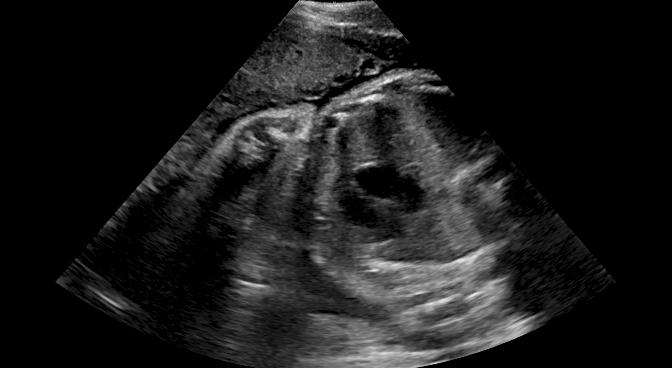

Fig. 6 compares the shadow confidence maps of the state-of-the-art methods and the proposed methods. RW and have the same parameters as used for Table I. The shadow confidence maps of the baseline, the proposed method and the proposedAG method are generated directly from input shadow images by confidence estimation networks. Overall, the proposed method and the proposedAG method achieve more visually reasonable shadow confidence estimation than the baseline and the state-of-the-art on different anatomical structures shown in Fig. 6. The proposed method and the proposedAG method are able to highlight multiple shadow regions while the RW algorithm shows limitations for most cases, especially for disjoint shadow regions.

Row I in Fig. 6 shows a fetal brain image from . The confidence estimation of shadow regions from the baseline, the proposed method and the proposedAG method are similarly accurate since we use fetal brain images to train the confidence estimation networks in these three methods. These outperform [16] and [22]. Rows (II-IV) in Fig. 6 show shadow confidence maps of non-brain anatomy from , including lips, abdominal and cardiac. The baseline failed on unseen data during inference. However, the proposed methods are able to generate accurate shadow confidence maps because of the generalized shadow features obtained by the shadow-seg module. Furthermore, the “Lips” example shows that our method is capable of detecting weaker shadow regions that have not been annotated in manual segmentation. This indicates that the confidence estimation network has learned general properties of shadow regions.

-D Alternative Examples of Shadow Confidence Estimation

We show an alternative group of examples for the confidence estimation of shadow regions (shown in Fig. 14). These examples include fetal brain from , and cardiac, lips, kidney from . Similar to the Fig. 6 in the main paper, Fig. 14 shows that the baseline fails to handle unseen data while the proposed method and the proposedAG method are able to predict pixel-wise confidence of multiple shadow regions. These examples demonstrate that the shadow-seg module is able to generalize the shadow representation and transfer shadow representation from the shadow/shadow-free classification task to a confidence estimation task.